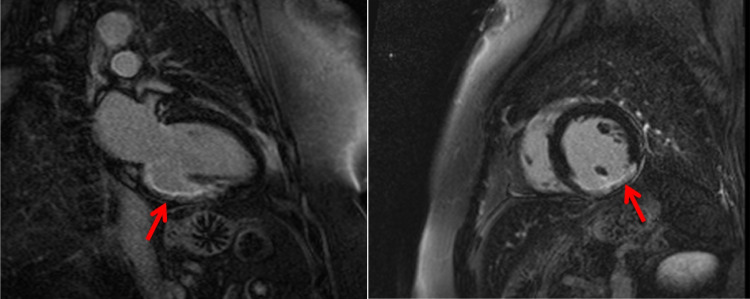

Thromboembolism arising from left atrial appendage and atrium (namely in association with atrial fibrillation), left ventricle, mitral or aortic valves, vegetations, tumours or proximal coronary artery is a possible cause for MINOCA (Fig. 1). Coronary thromboembolism has been found to be associated to MINOCA in up to 2.9% [17, 18]. Hypercoagulable states such as pregnancy, autoimmune disorders (antiphospholipid syndrome), heparin-induced thrombocytopenia, thrombotic thrombocytopenic purpura or active malignancy are possible causes for arterial and venous thrombosis [5••, 6••] that must be considered as hypothesis and searched when other causes are absent.

Fig. 1.

A 65-year-old man with history of hypertension presented with chest pain and ECG with ST segment elevation in DII and aVF leads. Invasive coronary angiography showed non-obstructive coronary disease, and subsequent troponin was raised. Mid-basal Inferior wall was hypokinetic on echocardiography. Cardiac magnetic resonance showed subendocardial late gadolinium enhancement (arrows) at the mid-basal inferior wall confirming an ischaemic pattern from myocardial infarction. A 24-h Holter revealed paroxysmal atrial fibrillation suggesting embolic aetiology. At 3-month follow-up, LV was mildly dilated and the ejection fraction was 38%, with NYHA functional class II